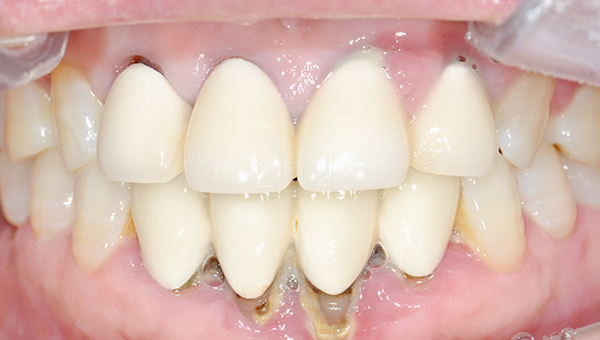

안*명 임플란트 시술 사례

상악 전체/ 하악 구치부 임플란트

2024.10.11

치료 전

2025.04.14

치료 후